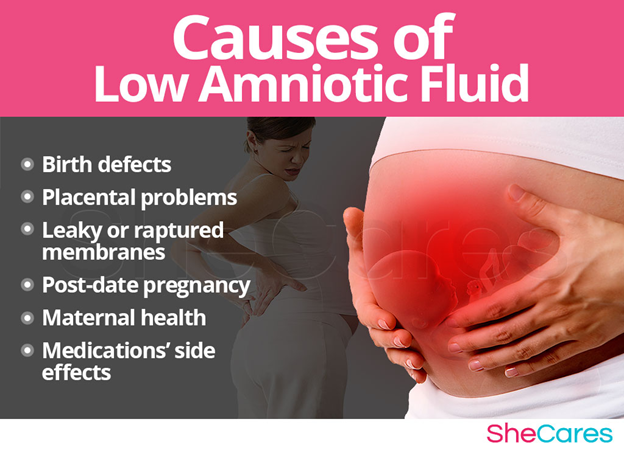

Amniotic fluid is a liquid that surrounds babies in the womb. It helps them grow and develop properly. Low amniotic fluid signs, or oligohydramnios, means